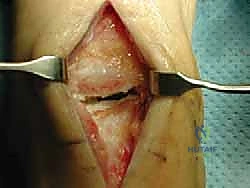

3. إعداد سرير الطعم (Preparation of the Recipient Site)

- يتم استخدام أدوات حفر أسطوانية دقيقة جداً لإزالة الغضروف المتآكل والعظم الميت تحته، وصولاً إلى العظم الصحي والحيوي الذي ينزف دماً (لضمان التروية الدموية للطعم الجديد).

صور إضافية من داخل غرفة العمليات والخطوات الجراحية

ندرك أهمية توثيق الخطوات الجراحية لطلاب الطب والمرضى الراغبين في فهم دقة الإجراء. هذه الصور توضح مراحل زراعة وتثبيت الطعم العظمي الغضروفي بدقة متناهية تحت إشراف أ.د. محمد هطيف.